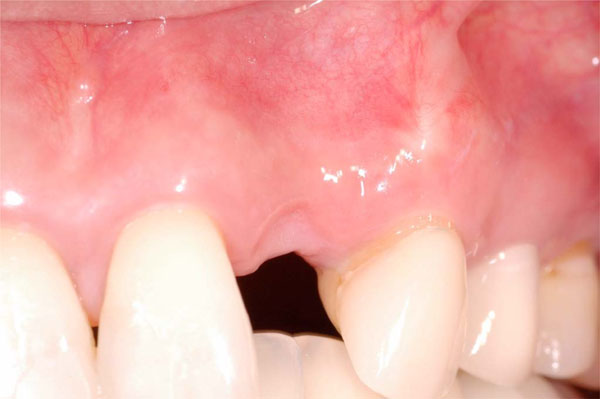

Extraction site defect 6 months after tooth removal without ridge preservation. Note buccal depression and loss of vertical height at site #10.

Esthetic defect caused by tooth loss without ridge preservation requiring guided bone regeneration to adequately place an implant at the #10 site for an acceptable outcome (occlusal view).

As previously mentioned, the extraction of a tooth frequently led to a deficiency in ridge width and height of the alveolar crest, which affected the optimal placement of an implant (Fig. 2). Allegrini et al. reported that ridge preservation decreased early alveolar ridge width loss after tooth extraction. Bone replacement grafts for ridge preservation are defined by the American Dental Association as osseous autograft, allograft or non-osseous graft placed in an extraction site at the time of extraction to preserve ridge integrity. The success of bone grafting procedures is ultimately dependent upon revascularization and remodeling of the grafted bone into vital, load bearing bone. Autografts and other bone substitutes, allografts, xenografts, synthetic biomaterials and osteoactive agents help restore alveolar bone loss or maintain dental alveolar bone after extraction, supporting optimal placement of dental implants [17].